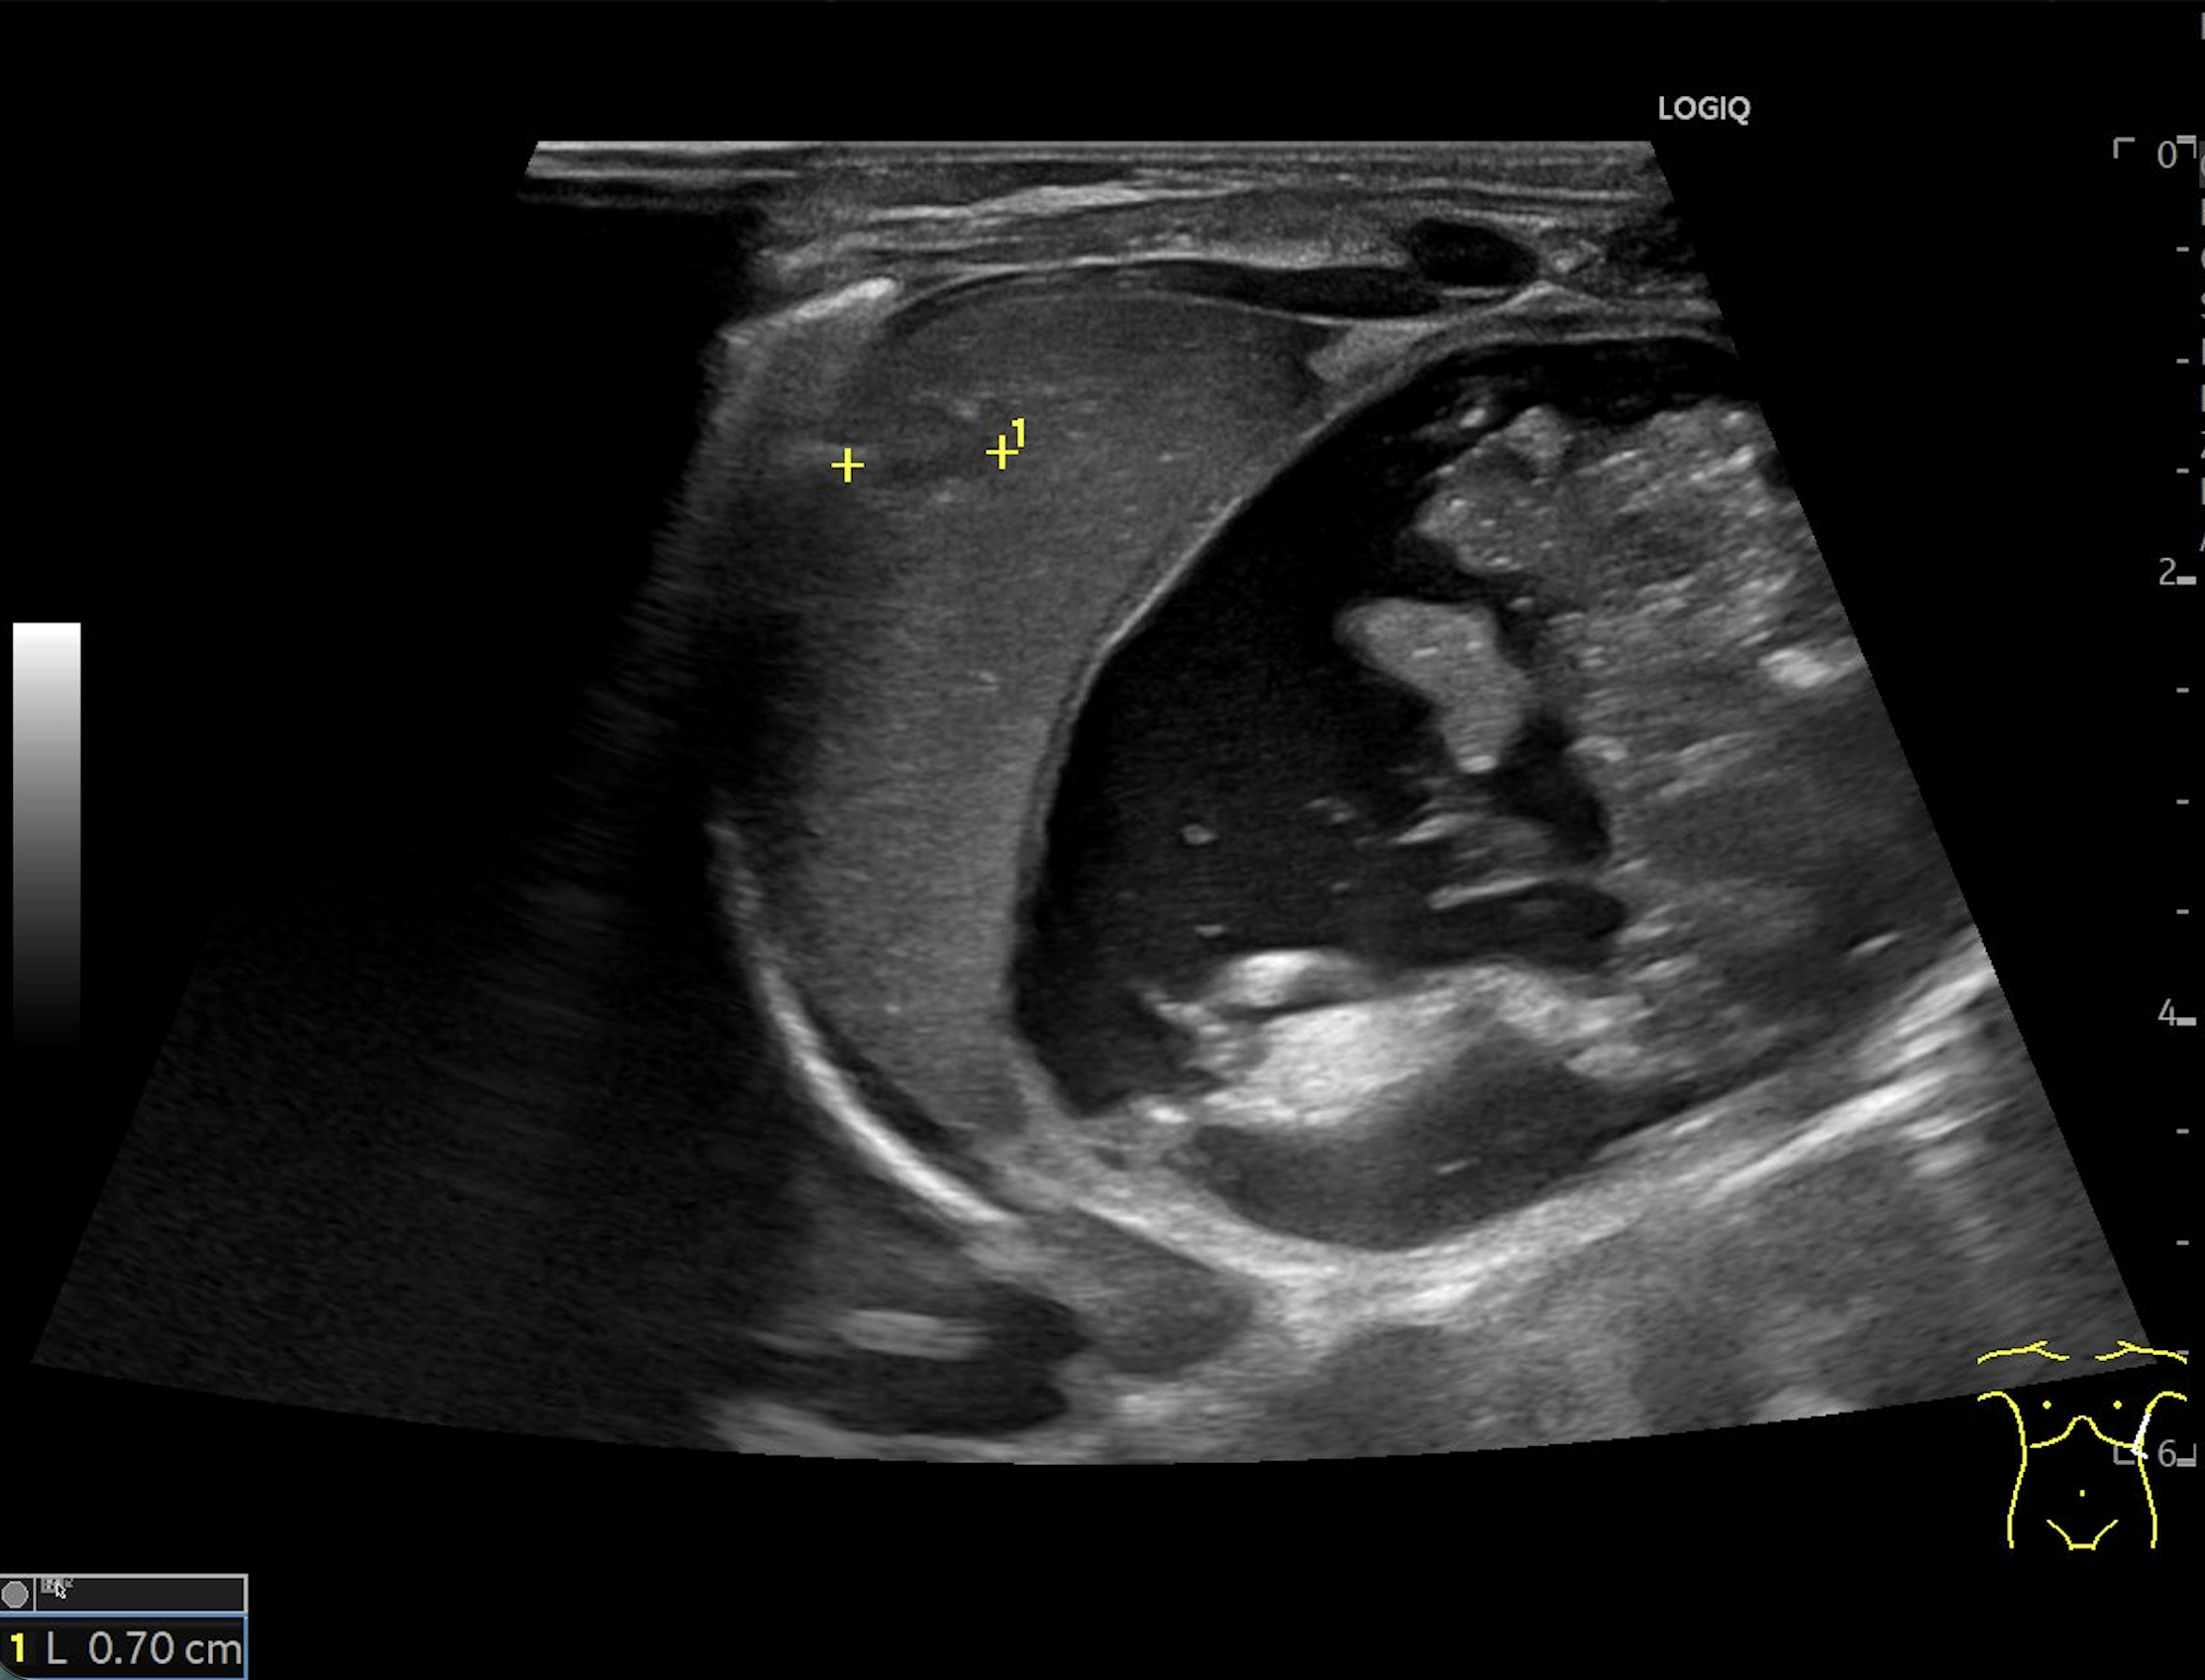

E: B-mode image in the coronal plane, showing a slightly heterogeneous lesion in the spleen, most consistent with a splenic hemangioma.

A lesion with heterogeneous echogenicity – most consistent with a splenic hemangioma- was also identified in the spleen (E). Follow-up ultrasound examination demonstrated rapid regression of the HH (F2-3).